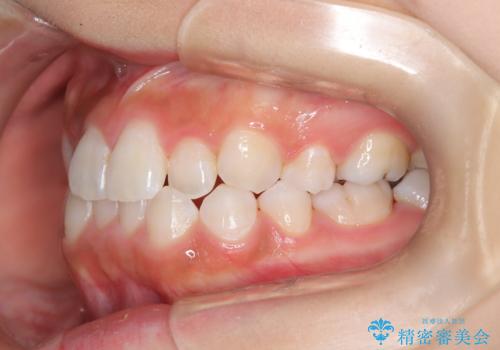

- 子供のころに矯正治療をされていたが、後戻りをしてしまったという20代女性の患者様です。上顎左右の2番が、咬合時に下顎の歯よりも内側に入っているクロスバイトという状態でした。奥歯の咬合関係は変えずに、マウスピース矯正にて前歯の並びを綺麗なアーチに仕上げました。再度後戻りしてしまうリスクを軽減させるために、リテーナー(保定装置)をお渡ししています。